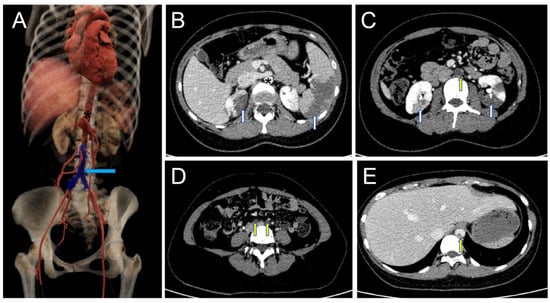

A Rare Case of Complete Myxoma Detachment Leading to Abdominal Aortic Occlusion and Secondary Visceral Necrosis: A Case Description and an Analysis of the Literature

2. Case Report